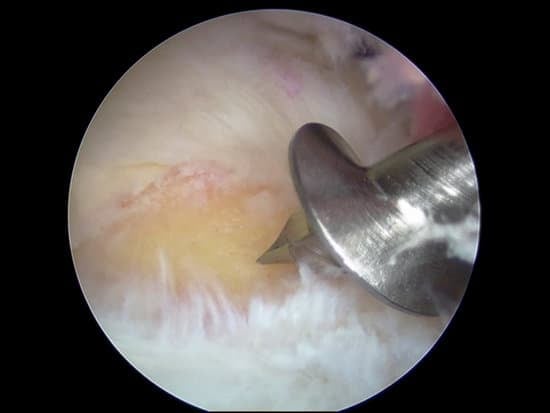

앵커(Anchor)는 어깨 관절경 수술에서 파열된 회전근개나 인대를 뼈에 견고하게 고정하는 데 사용됩니다.

사용 사례: 회전근개 파열의 복구 등에서 널리 사용됩니다.